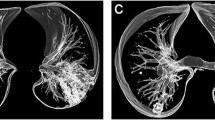

The imaging findings assessed on MRI and CT scans for this study are summarized in Table 2. The predominant patterns of parenchymal involvement according to CT versus MRI were: GGOs in 27 of 52 cases (51.9%) vs. 32 of 52 cases (61.5%), interlobular septal thickening in 17 of 52 cases (32.7%) vs. 17 of 52 cases (32.7%), and consolidation in two of 52 cases (3.8%) vs. two of 52 cases (3.8%). At least one additional finding was present in 41 of 52 cases (78.8%) according to CT and in 47 of 52 cases (90.4%) according to MRI. No pulmonary findings were observed in five of 52 cases (9.6%) using CT and in one of 52 cases (1.9%) using MRI. DWI was positive for high suspicion of inflammatory activity in 23 to 50 cases (46.0%); 19 of whom also had GGOs (Fig. 1). Agreement between CT and MRI when evaluating the presence of different imaging findings, as assessed with Cohen’s k, was very high for consolidation (k = 1.000); substantial for interlobular septal thickening (k = 0.734); poor for GGOs (k = 0.339), fibrotic changes (k = 0.224), pleural indentation (k = 0.231), vessel enlargement (k = 0.339), and bronchiolar ectasia (k = 0.000). The degree of agreement between CT and MRI in identifying the predominant pattern was substantial (k = 0.764).

The sensitivity, specificity, accuracy, and positive and negative predictive values of MRI, when considering CT as the standard of reference, in the detection of different parenchymal patterns are detailed in Table 3. The sensitivity was highest for interlobular septal thickening (1.00, 95% confidence interval (CI): 0.91–1.00), consolidation (1.00, 95% CI: 0.63–1.00), and GGOs (1.00, 95% CI: 0.91–1.00) (Fig. 2). Conversely, MRI showed poor sensitivity in the detection of fibrosis (0.18, 95% CI: 0.04–0.43), pleural indentation (0.23, 95% CI: 0.09–0.44), vessel enlargement (0.50, 95% CI: 0.07–0.93), and bronchiolar ectasia (0.00, 95% CI: 0.00–0.18). Specificity was overall very high, except for GGOs (0.25, 95% CI: 0.05–0.57) and interlobular septal thickening (0.64, 95% CI: 0.31–0.89). MRI was not able to detect bronchiolar ectasia in any of the cases.

The main disease pattern, among GGOs, consolidation, interlobular septal thickening, and fibrosis, was detected by both MRI and CT with substantial agreement (k = 0.764). Also, MRI proved to be very reliable in assessing the resolution or progression of radiological signs relative to the previous CT scan, showing almost perfect agreement (k = 0.857) with CT. Of note, very good agreement was confirmed for consolidation and interlobular septal thickening (k = 1.00 and k = 0.734, respectively). However, poor agreement was noted concerning the detection of GGOs (k = 0.339), which pathologically corresponds to partial filling of the alveolar lumen with fluid, macrophages, neutrophils, or amorphous material and which correlates with disease activity [23]. The poor agreement between MRI and CT in the detection of GGOs could be explained by MRI’s greater ability to discriminate the alveolar content by quantifying its PD, showing a relatively much higher signal in lung parenchyma affected by endo-alveolar effusion when compared with normally aerated lungs (Fig. 3). Accordingly, the sensitivity for MRI in detecting GGOs was perfect (1.00, 95% CI: 0.91–1.00) as compared with the very low specificity (0.25, 95% CI: 0.05–0.57). Separately, it is noteworthy that very poor agreement was recorded for the detection of bronchiolar ectasia (k = 0.000). These data confirm previous findings by Ciet et al. [24], who reported the superior sensitivity of CT when evaluating changes in the peripheral areas of the lung, such as bronchiolar ectasia. A possible explanation for this could be the lower spatial resolution of MRI as compared with CT, especially when focusing on more distal areas of the lung [25]. To overcome the issue, three-dimensional T1-weighted, gradient-echo sequences might be added to the protocol. However, further studies are necessary to confirm these radiologic and pathologic correlations.